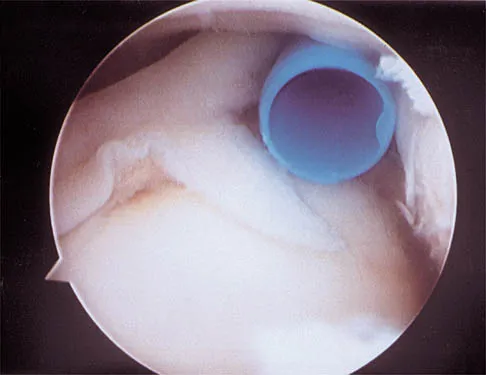

Question 76

A 21-year-old collegiate pitcher has had pain in his dominant shoulder for the past 3 months despite management consisting of rest, rehabilitation, and an analysis of throwing mechanics. An arthroscopic photograph from the posterior portal is shown in Figure 10. The biceps anchor to the bone was not detached to probing. Treatment of the lesion to the left of the cannula should consist of arthroscopic

Explanation